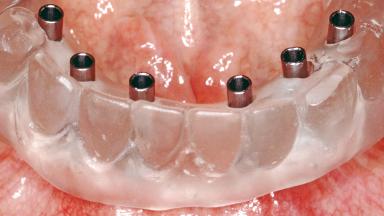

Conventional Loading of Six Implants in the Mandible and Final Restoration with a Full-Arch Metal-Ceramic FDP

# of Implants 6

Type of Implants One-Piece

Prosthesis Type FDP

Retention Screw-retained, with 4 or more splinted implants Screw-retained, with 4 or more splinted implants